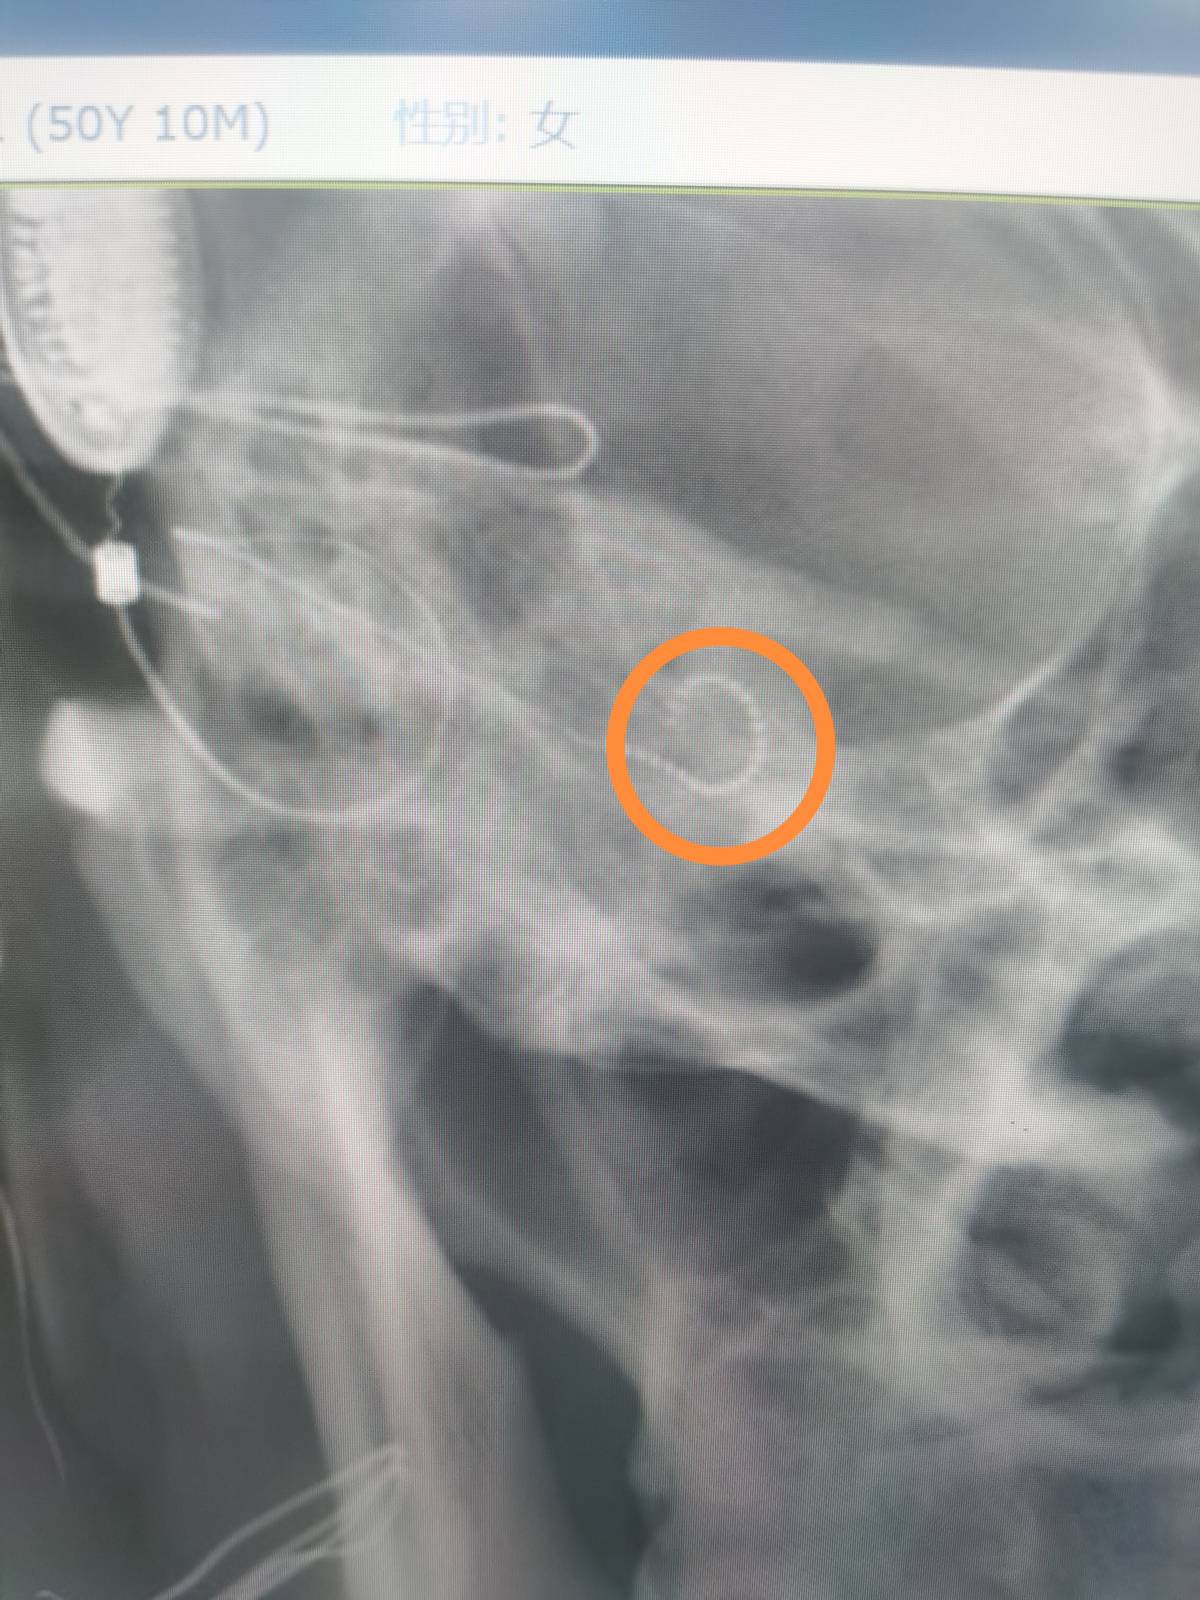

近日,太阳成集团tyc33455cc附属第一医院耳鼻咽喉科同一天给两例患有双侧极重度感音神经性耳聋而佩戴助听器无效的患者开展人工耳蜗植入术,这也是衡阳市自主开展的第一例和第二例人工耳蜗植入术。此手术在科室主任江青山教授的指导下,由科室副主任陈祖尧博士主刀完成,手术顺利,术中电极阻抗测量以及神经反应测试皆为正常,术后第二天的头颅X片提示植入电极在耳蜗内布阵良好,表明手术取得了成功。患者需要做的就是等待一个月以后的开机调试和言语康复。

人工耳蜗电极

术后颅骨X片显示耳蜗植入电极位置正常